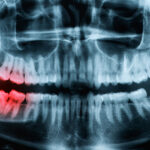

歯ぎしり・食いしばり

睡眠中、ギシギシ、ギリギリと音を立てて歯をすり合わせる「歯ぎしり」や、上下の歯を ...